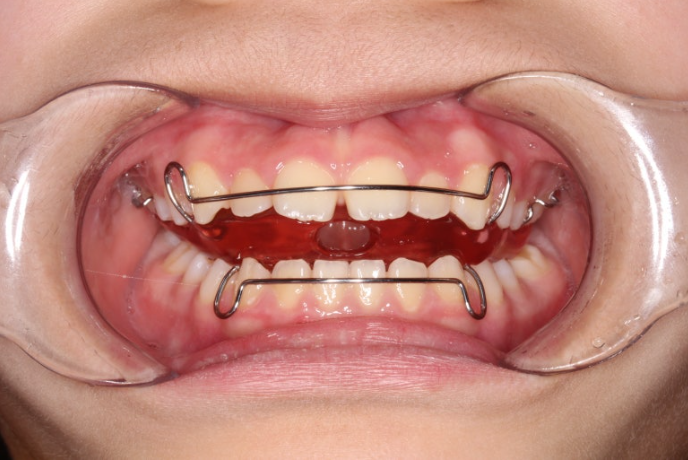

모노블록 장치는 이렇게 생겼습니다.

위 아래가 한덩어리로 된 장치라서 장치를 낀채로 말을 할 수 없고 비염이 있을 때 입으로 숨을 쉬어야 하는 상황에서는 장치를 끼기 힘든 단점이 있습니다.